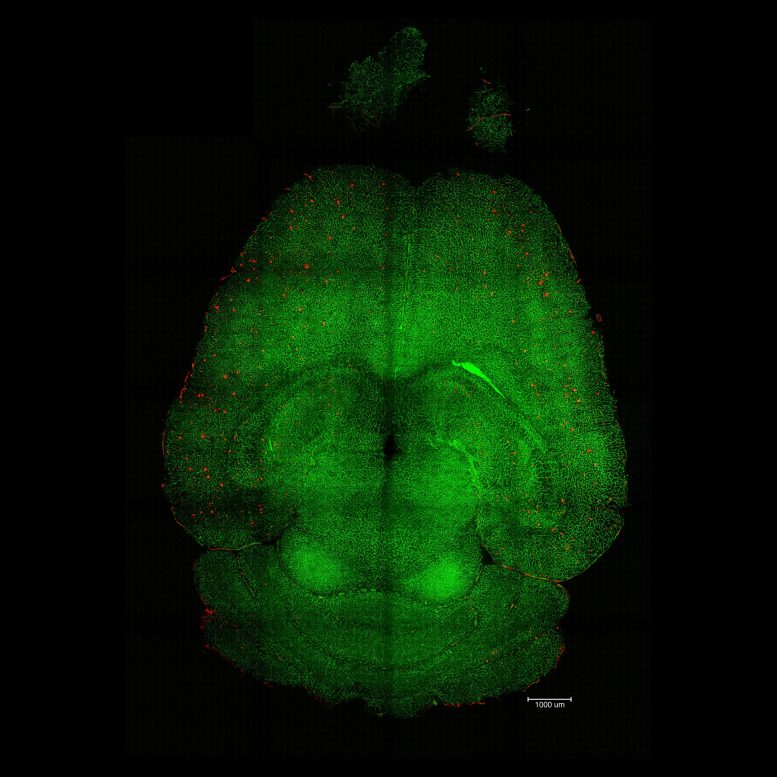

Light sheet fluorescence microscope images of mouse brain 12h after NOT being treated with nanoparticles. The brains were analyzed to see the amount of Aβ plaques accumulation. Red: Aβ plaques. Green: vessels from the blood brain barrier. Credit: Institute for Bioengineering of Catalonia (IBEC)The blood-brain barrier acts as a gatekeeper between the bloodstream and brain tissue, shielding it from harmful substances such as toxins or pathogens. The research team found that by targeting a specific biological pathway, they could help the brain clear out “waste proteins” that normally accumulate and cause damage. In Alzheimer’s disease, one of the main culprits is amyloid-β (Aβ), a protein that builds up between neurons and disrupts their communication and function.

Light sheet fluorescence microscope image of mthe ouse brain 12h after being treated with nanoparticles. The brains were analyzed to see the amount of Aβ plaque accumulation. Red: Aβ plaques. Green: vessels from the blood-brain barrier. Credit: Institute for Bioengineering of Catalonia (IBEC)The most striking data were the therapeutic effects. Researchers conducted various experiments to analyze the behavior of the animals and measure their memory decline over several months, covering all stages of the disease. In one of the experiments, they treated a 12-month-old mouse (equivalent to a 60-year-old human) with the nanoparticles and analyzed its behavior after 6 months. The result was impressive: the animal, aged 18 months (comparable to a 90-year-old human), had recovered the behavior of a healthy mouse.